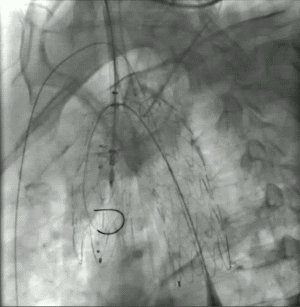

★ 病例3:弓部动脉瘤伴大量附壁血栓

该病例动脉瘤内有大量附壁血栓,一旦术中血栓脱落,可能导致脑梗死或者栓塞。

主体支架顺利通过主动脉弓准确定位释放,各分支依次延导丝进入内嵌通道后释放。治疗效果良好,没有任何卒中和栓塞。

★ 病例4:主动脉夹层真腔狭窄

该病例主动脉弓部真腔严重狭窄受压,有可能影响主体支架的释放和寻找分支通道。

与主体支架一体化的无名动脉外分支和凹陷区域,留出空间用于置管和容纳单独的分支支架。手术操作简单,效果良好。